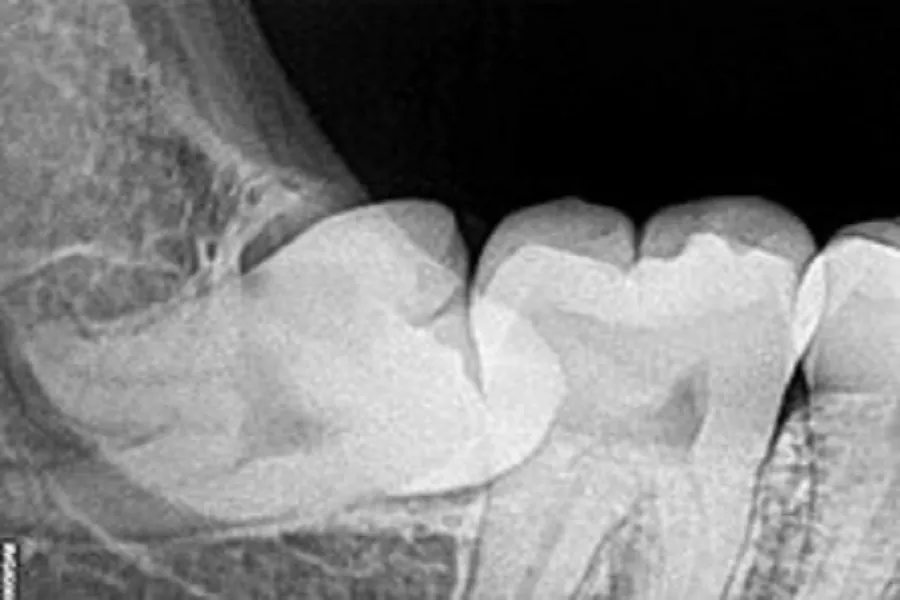

The structure of the mandible cannot be adequately exercised for chewing function, and it gradually degenerates. The amount of teeth is larger than that of the mandible. In this way, when the third molars grow out, the position is often not enough, so that it is difficult to erupt, which forms “impacted wisdom teeth”, wisdom teeth Impaction is a common disease among young adults. Impacted wisdom teeth can cause irregular dentition, infection of the coronal space, difficulty in opening the mouth, caries of the second molar, and in severe cases, osteomyelitis of the jaw. If a wisdom tooth is found to be impacted and repeatedly causes inflammation, it should be removed as soon as possible to avoid other symptoms or diseases. What are the hazards of impacted wisdom teeth? Wisdom teeth are human third molars, which generally erupt at the age of 18-25. Due to the degeneration of the human jaw, and the corresponding change in the size and number of teeth, the third molars that erupted at last are often impacted because there is no room for eruption, which is manifested as partial eruption, improper eruption, and complete buried impaction. . The incidence of impacted wisdom teeth is high, and its harm is mainly manifested in the following points.

In addition, if the wisdom teeth do not grow, the residual tooth germs may degenerate and form oral tumors. When there is insufficient space, the tooth germs may absorb the roots of the second molars in front of them, reducing their strength and affecting their function. Ectopic or eruption Incomplete wisdom teeth also often interfere with normal occlusion. The muscles that affect the mandible must often contract abnormally to avoid this interference, which makes muscles and joints prone to inflammation and pain.

(2) caries. The misplaced wisdom teeth and the second molars are prone to accumulation of food residues, and it is not easy to clean. Generally, dental caries can form in a few months, directly destroying the tooth tissue.